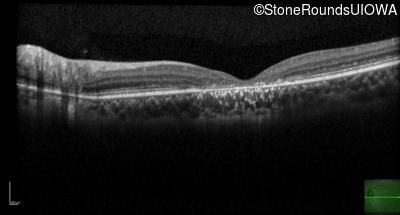

Optical Coherence Tomography - Right - 20/160 +1

Exemplar / OCT Stack

Optical Coherence Tomography - Left - 20/125 -1